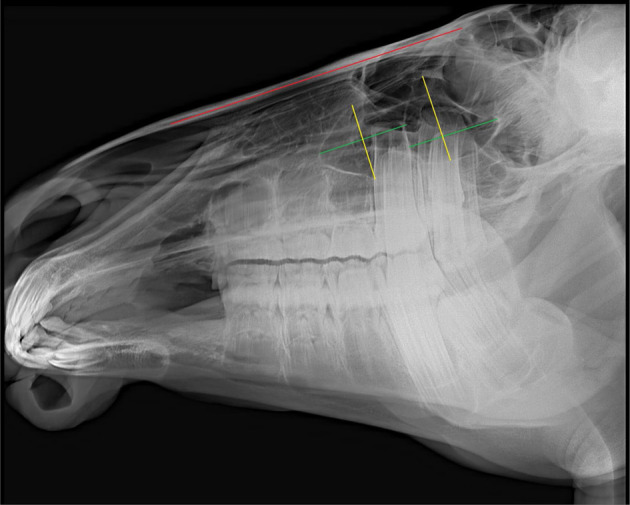

Dareshuri马是伊朗法尔斯省的主要品种。虽然影响上颌颊齿和上颌窦的疾病相对常见,但关于这些结构在不同年龄的尺寸和关系的基础数据有限。考虑到年轻马的头部在成熟过程中发生了显著的解剖学变化,本研究旨在评估上颌颊齿在吻侧和尾侧鼻窦(分别为RMS和CMS)内的位置和解剖关系的年龄相关变化,以及在其生长过程中单个鼻窦室的长度和高度的变化。研究人员对29匹年龄在4个月至5岁之间的健康活马的头部进行了放射线照相,并使用EConsole1放射线照相查看器软件(V.3, 2017, DRTECH Europe GmbH, Schwalbach am Taunus,德国)进行了分析。统计分析显示,整个研究中唯一显著的变化是CMS长度的增加(4.075±0.99 cm; SE),这在3岁以下的马中更为显著。在不到1岁时,上颌窦中唯一存在的牙齿是M1。1 ~ 2岁时,M2进入上颌隔室;PM4在2 ~ 3岁进入RMS, M3在3 ~ 4岁进入CMS。最终,在4 ~ 5岁时,PM3、M1和M2出现在RMS中,M2和M3出现在CMS中。本研究结果对临床上颌面部疾病的诊断和治疗具有一定的参考价值,并可作为进一步解剖研究的参考。

Dareshuri horses are the predominant breed in Fars Province, Iran. Although disorders affecting their maxillary cheek teeth and maxillary sinuses are relatively common, limited fundamental data are available on the dimensions and relationships of these structures at different ages. Given the significant anatomical changes in the heads of young horses as they mature, this study aimed to evaluate age-related changes in the position and anatomical relationships of individual maxillary cheek teeth within the rostral and caudal maxillary sinuses (RMS and CMS, respectively), as well as changes in the lengths and heights of individual sinus compartments during their growth. Radiographs were performed on 29 heads of live, healthy horses aged between 4 months and 5 years and were analyzed using the EConsole1 Radiography Viewer software (V.3, 2017, DRTECH Europe GmbH, Schwalbach am Taunus, Germany). Statistical analyses revealed that the only significant change throughout the study was an increase in the length of the CMS (4.075 ± 0.99 cm; SE), which was more significant in horses up to three years old. At less than 1 year old, the only tooth present in the maxillary sinus was M1. At 1-2 years old, M2 was observed entering the maxillary compartments; PM4 entered the RMS at 2-3 years old, and M3 entered the CMS at 3-4 years old. Eventually at 4-5 years old, PM3, M1, and M2 were present in the RMS, and M2 and M3 were present in the CMS. This information should be of value in the diagnosis and treatment of Dareshuri maxillofacial disorders and used as a reference for further anatomical investigations.